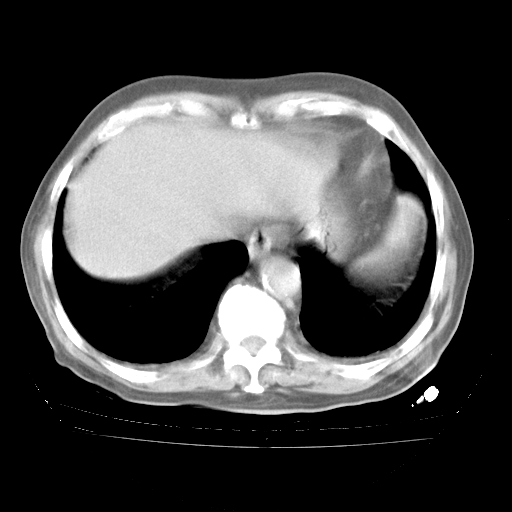

4月28日肺部CT——再次出现类似去年5月9日——透光度降低,“间质性”改变。

4月28日肺部CT——再次出现类似去年5月9日——磨玻璃样、间有“粟粒样”改变。

4月28日肺部CT